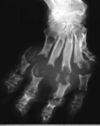

90

identify

Feline digit-lung syndrome Primary neoplasia in lungs that causes Lytic changes in digital bones. We dont know why this happens in cats.

91

Hyperthrophic osteopathy in dogs Primary neoplasia in thorax or abdominal cavity that affects long bones. Makes them "hairy".